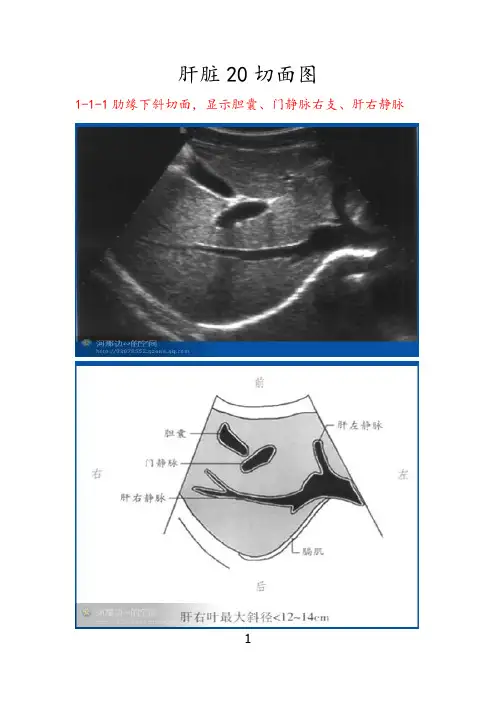

肝脏20切面图1-1-1肋缘下斜切面,显示胆囊、门静脉右支、肝右静脉11-I-2肋缘下斜切面,显示下腔静脉、肝左静脉、肝中静脉、肝右静脉21-1-3剑下肝左叶斜切面,显示肝圆韧带、腹主动脉、下腔静脉、门静脉31-1-4剑下肝左叶斜切面,显示肝左叶、肝尾状叶、静脉韧带、腹主动脉、下腔静脉41-1-5右第五肋间斜切面,显示门静脉、肝左静脉外下段、门静脉左支外上段、肝左静脉51-1-6右第六或第七肋间斜切面,显示右肝管、肝总管及胆总管、肝动脉、门静脉、下腔静脉6管、右肝管、下腔静脉、肝右静脉7左肝管、右肝管、下腔静脉、肝圆韧带81-1-9经下腔静脉肝左叶矢状切面,显示下腔静脉、门静脉矢状部、肝左静脉、左叶间静脉、肠系膜上静脉91-1-10经腹主动脉肝左叶矢状切面,显示腹主动脉、肝左静脉、门静脉、脾动脉、脾静脉、腹腔动脉101-1-11剑下肝左叶斜切面静脉左支矢状部、显示胆囊、肝圆韧带、门静脉左支横部、左外叶下段支、左外叶上段支、静脉韧带、下腔静脉111-1-12肝左叶矢状切面,显示下腔静脉、门静脉、肝左静脉、静脉韧带121-1-13肝右叶矢状切面,显示下腔静脉、肝中静脉、门静脉右支、右肾静脉、右肾动脉131-1-14肝右叶纵切面,显示与右肾的界面141-1-15肝右叶纵切面,显示隔顶部与胸腔15161-1-16肝左叶横切面,显示静脉韧带、腹主动脉、下腔静脉、尾状叶171-1-17肝左叶横切面,显示肝圆韧带181-1-18右肝横切面,显示门静脉左右支191-1-19肋缘下右肝横切面,显示右肝下缘201一1-20肝右叶横切面,显示隔顶部与胸腔2122。

肝脏20切面图1-1-1肋缘下斜切面,显示胆囊、门静脉右支、肝右静脉1-I-2肋缘下斜切面,显示下腔静脉、肝左静脉、肝中静脉、肝右静脉1-1-3剑下肝左叶斜切面,显示肝圆韧带、腹主动脉、下腔静脉、门静脉1-1-4剑下肝左叶斜切面,显示肝左叶、肝尾状叶、静脉韧带、腹主动脉、下腔静脉1-1-5右第五肋间斜切面,显示门静脉、肝左静脉外下段、门静脉左支外上段、肝左静脉1-1-6右第六或第七肋间斜切面,显示右肝管、肝总管及胆总管、肝动脉、门静脉、下腔静脉1-1-7经第一肝门右肋下斜切面,显示胆囊、门静脉、左肝管、右肝管、下腔静脉、肝右静脉1-1-8经第一肝门右肋下斜切面,显示腹主动脉、门静脉、左肝管、右肝管、下腔静脉、肝圆韧带1-1-9经下腔静脉肝左叶矢状切面,显示下腔静脉、门静脉矢状部、肝左静脉、左叶间静脉、肠系膜上静脉1-1-10经腹主动脉肝左叶矢状切面,显示腹主动脉、肝左静脉、门静脉、脾动脉、脾静脉、腹腔动脉1-1-11剑下肝左叶斜切面静脉左支矢状部、显示胆囊、肝圆韧带、门静脉左支横部、左外叶下段支、左外叶上段支、静脉韧带、下腔静脉1-1-12肝左叶矢状切面,显示下腔静脉、门静脉、肝左静脉、静脉韧带1-1-13肝右叶矢状切面,显示下腔静脉、肝中静脉、门静脉右支、右肾静脉、右肾动脉1-1-14肝右叶纵切面,显示与右肾的界面1-1-15肝右叶纵切面,显示隔顶部与胸腔1-1-16肝左叶横切面,显示静脉韧带、腹主动脉、下腔静脉、尾状叶1-1-17肝左叶横切面,显示肝圆韧带1-1-18右肝横切面,显示门静脉左右支1-1-19肋缘下右肝横切面,显示右肝下缘1一1-20肝右叶横切面,显示隔顶部与胸腔THANKS !!!致力为企业和个人提供合同协议,策划案计划书,学习课件等等打造全网一站式需求欢迎您的下载,资料仅供参考!。

肝脏20切面图

i-i-i肋缘下斜切面,显示胆囊、门静脉右支、肝右静脉

肝右叶最大斜径0 27』加